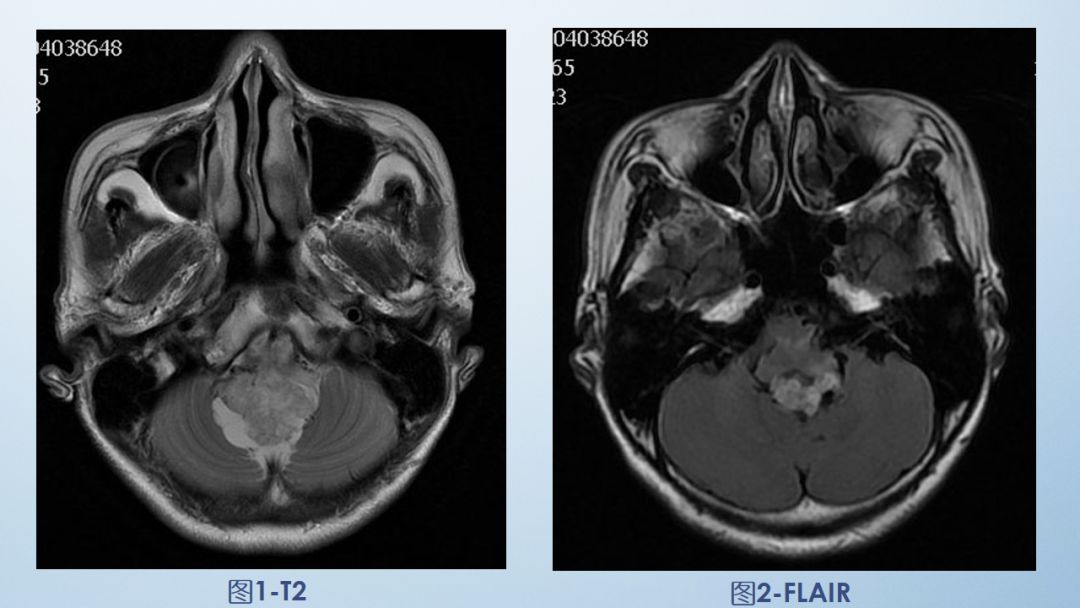

FLAIR图及T1矢状位增强:白色箭头所示小脑延髓池内可见实性占位病变,形态不规则,呈分叶状,病变边界清晰,边缘见血管流空信号影如蓝色箭头所示。

影像描述:小脑延髓池内见不规则异常信号影,呈等及稍长T1长T2信号,内部信号不均,边缘见稍粗大流空信号血管影,FLAIR病灶中心少许片状低信号,增强呈明显强化,DWI不均低信号,ADC不均高信号。小脑半球、延髓、第四脑室受压变形。临近延髓受压变窄,呈长T1长T2信号。